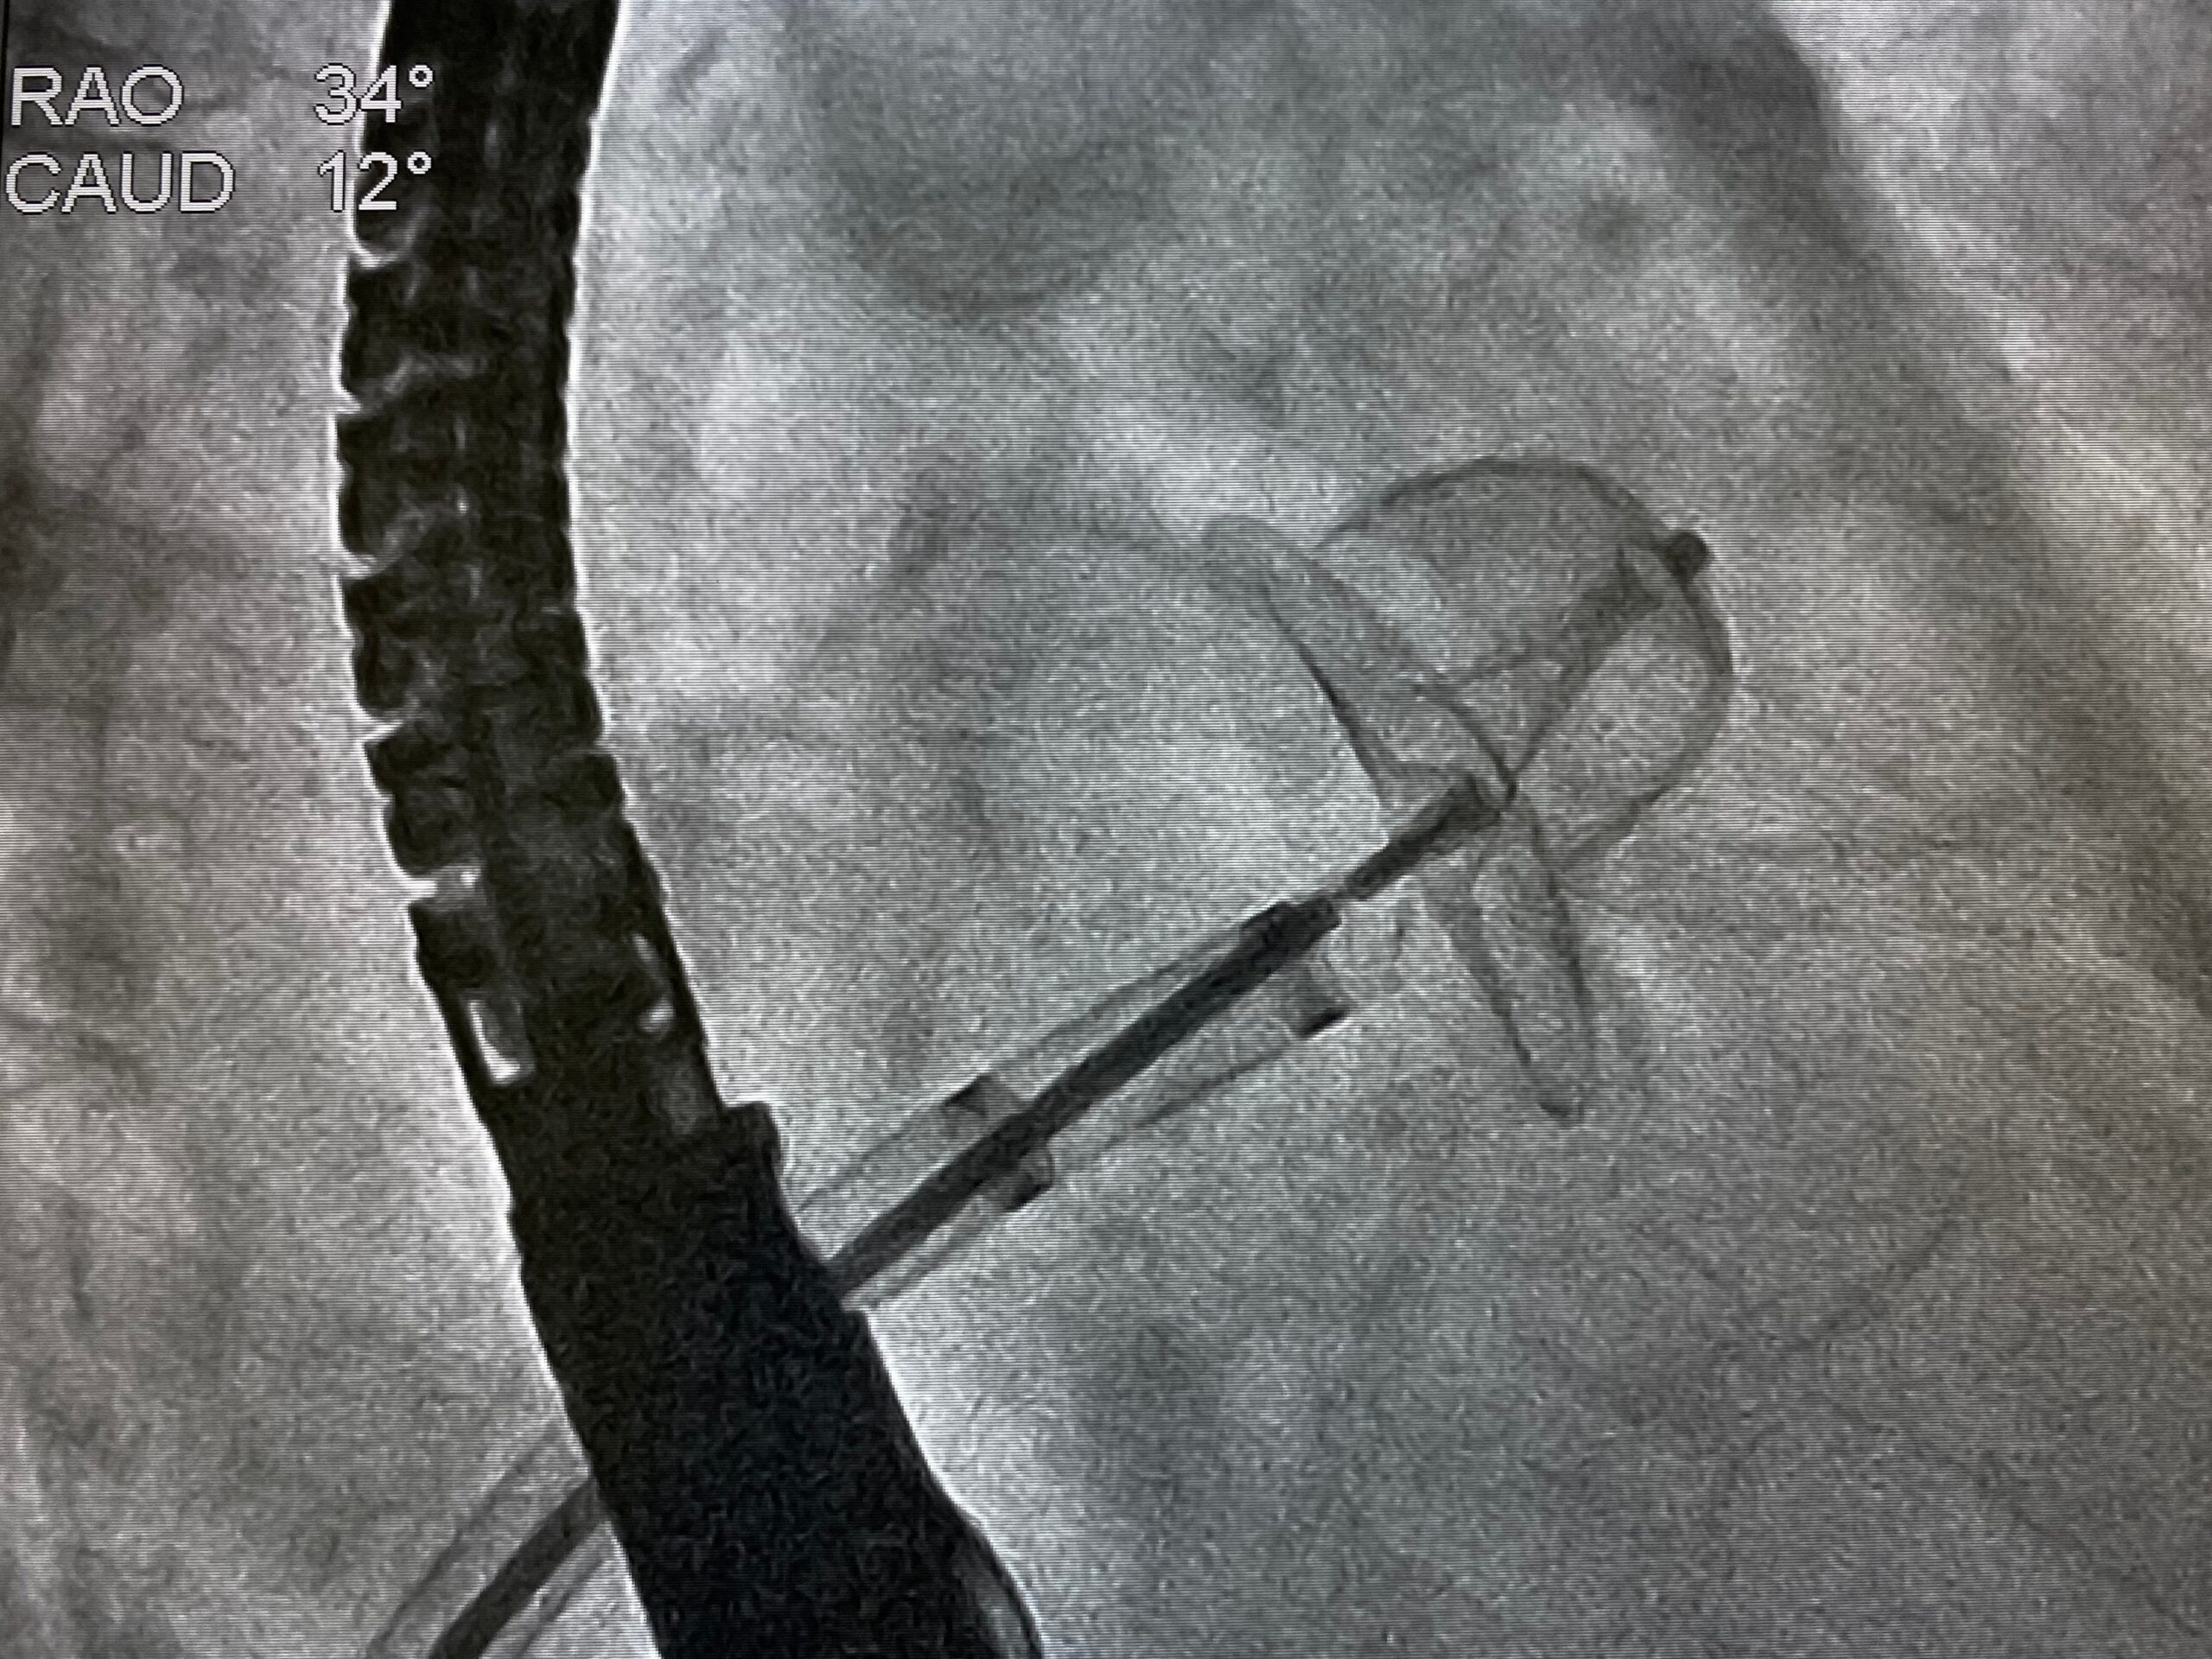

Physicians leveraged a surgical technique to achieve partial cardiac denervation, reducing the incidence of POAF post-CABG.